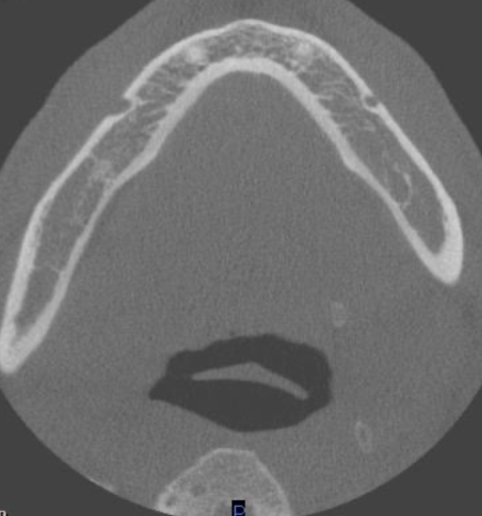

axial

what plane is this